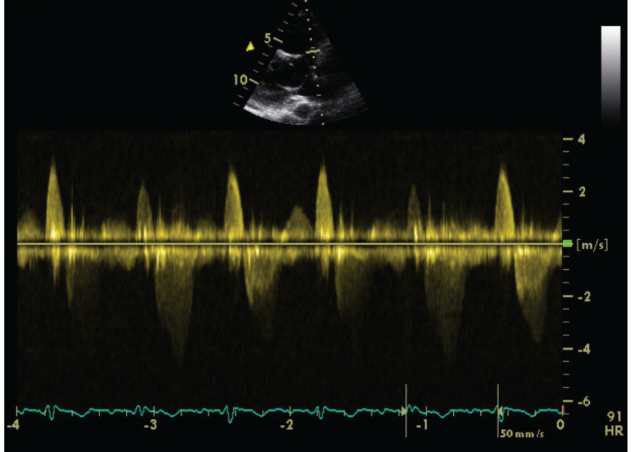

We carried out an Exercise Stress Echocardiogram using a semi-supine bicycle using WHO protocol using a 3-minute step protocol of 20-40 watts at 60-75rpm until volitional fatigue. All basic haemodynamic parameters were recorded at rest and at each stage of exercise (BP, heart rate, Oxygen saturation, electrocardiogram). We assessed his shunt in para-sternal long axis window (PLAX). Consultant cardiologist and senior cardiac physiologist carried out the test. We used colour doppler across interventricular septum to identify the VSD. Once it was identified, we tilted the probe to optimize VSD capture. Sample volume was then placed through VSD to obtain pulsed doppler images at rest (Figure 1). Similar pulsed doppler images were obtained at peak exercise (Figure 2). We did direct shunt volume assessment using velocity time integral (VTI). We averaged all VTIs obtained for five cardiac cycles.

Figure 1 Echocardiographic pulse wave doppler signal at rest.

Averaged VTI at rest for left to right (L-R) shunt was 26.32cm and at stress was 21.6cm. Similarly VTI at rest for right to left shunt (R-L) was 78.08cm and at stress was 79.44cm.